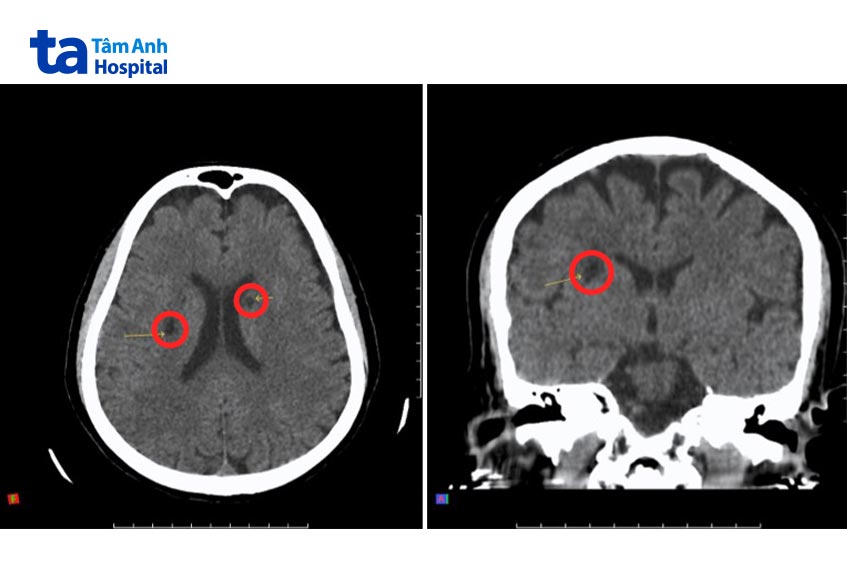

Nhận định người bệnh bị đột quỵ, BS.CKI Nguyễn Vinh Quang – Đơn vị Cấp cứu lập tức kích hoạt “Code Stroke” – quy trình khẩn cấp được thiết lập riêng cho xử trí đột quỵ. Người bệnh được chụp CT, MRI não đánh giá vùng não tổn thương. Hệ thống chụp CT hơn 100.000 lát cắt Somatom Force VB30 (Siemens, Đức) nhanh chóng loại trừ nguyên nhân xuất huyết não, xác định chẩn đoán nhồi máu não cấp trong thời gian vàng (trong vòng 4,5 giờ tính từ thời điểm khởi phát triệu chứng đột quỵ).

Ê kíp bác sĩ Cấp cứu hội chẩn với BS.CKI Hoàng Tuyết Sương – Đơn vị Thần kinh, chỉ định can thiệp cấp cứu cho người bệnh bằng thuốc tiêu sợi huyết. Tại thời điểm nhập viện, huyết áp của người bệnh ghi nhận ở mức rất cao 232/125 mmHg, do đó được xử lý thuốc để ổn định huyết áp trước. Sau đó, bác sĩ Sương tiến hành tiêm thuốc tiêu sợi huyết. Đây là phương pháp tiêm thuốc tiêu sợi huyết vào tĩnh mạch để làm tan cục máu đông gây tắc nghẽn mạch máu, thường được chỉ định trong các trường hợp đột quỵ nhồi máu não cấp.